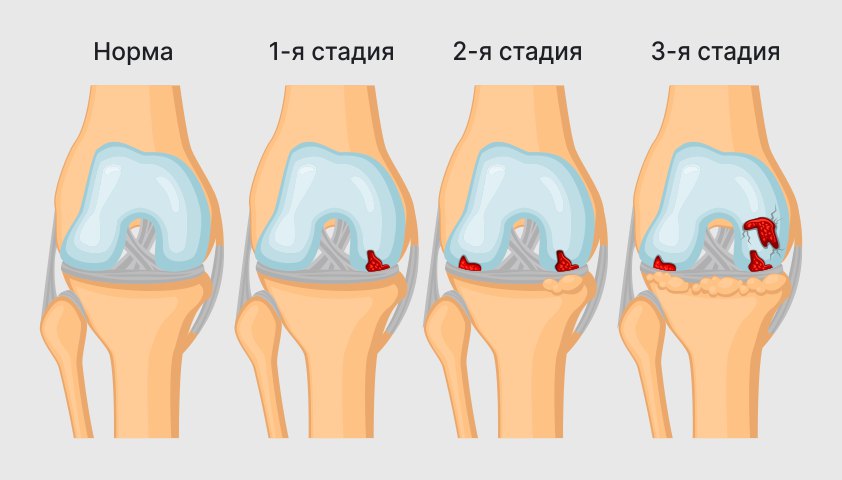

Суставная Жидкость и Головка Сустава: Обзор и Здоровье